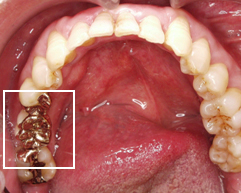

治療前

他医院にて接着ブリッジをしていた部分がはずれている状態。両隣の歯が薄く削られています。

左下1本、歯がありません。

抜けている歯の前後の歯は虫歯にもなっていません。